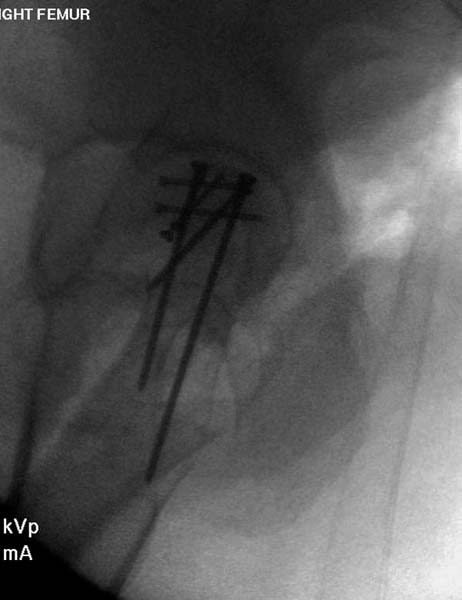

Больная стабильная после хирургических мероприятии и получив добро, приступили к закрытому вправлению таранной кости с укладкой наружного фиксатора. Затем укладка больную на бок и открытый остеосинтез перелома-вывиха головки бедра.

По характеру повреждения головка находится сзади и напрашивается задний Кохер-Лангенбек доступ, но в заднем доступе имеется риск повреждения магистрального кровоснабжения головки a. circumflexa. Более щадящая trochanteric flip (digastric osteotomy) сохранит кровоснабжение и дасть возможность работу при вывихнутом суставе.

Остеосинтез бедра не стали делать из-за множественных переломов ребер с ушибом грудной клетки и поэтом у закончили фиксацию бедра наружным фиксатором.

Около 11.00 вечера больная переведена в реанимацию, без сознания, но стабильная.. На третьий день провели стабилизацию перелома бедра антеградным остеосинтезом.